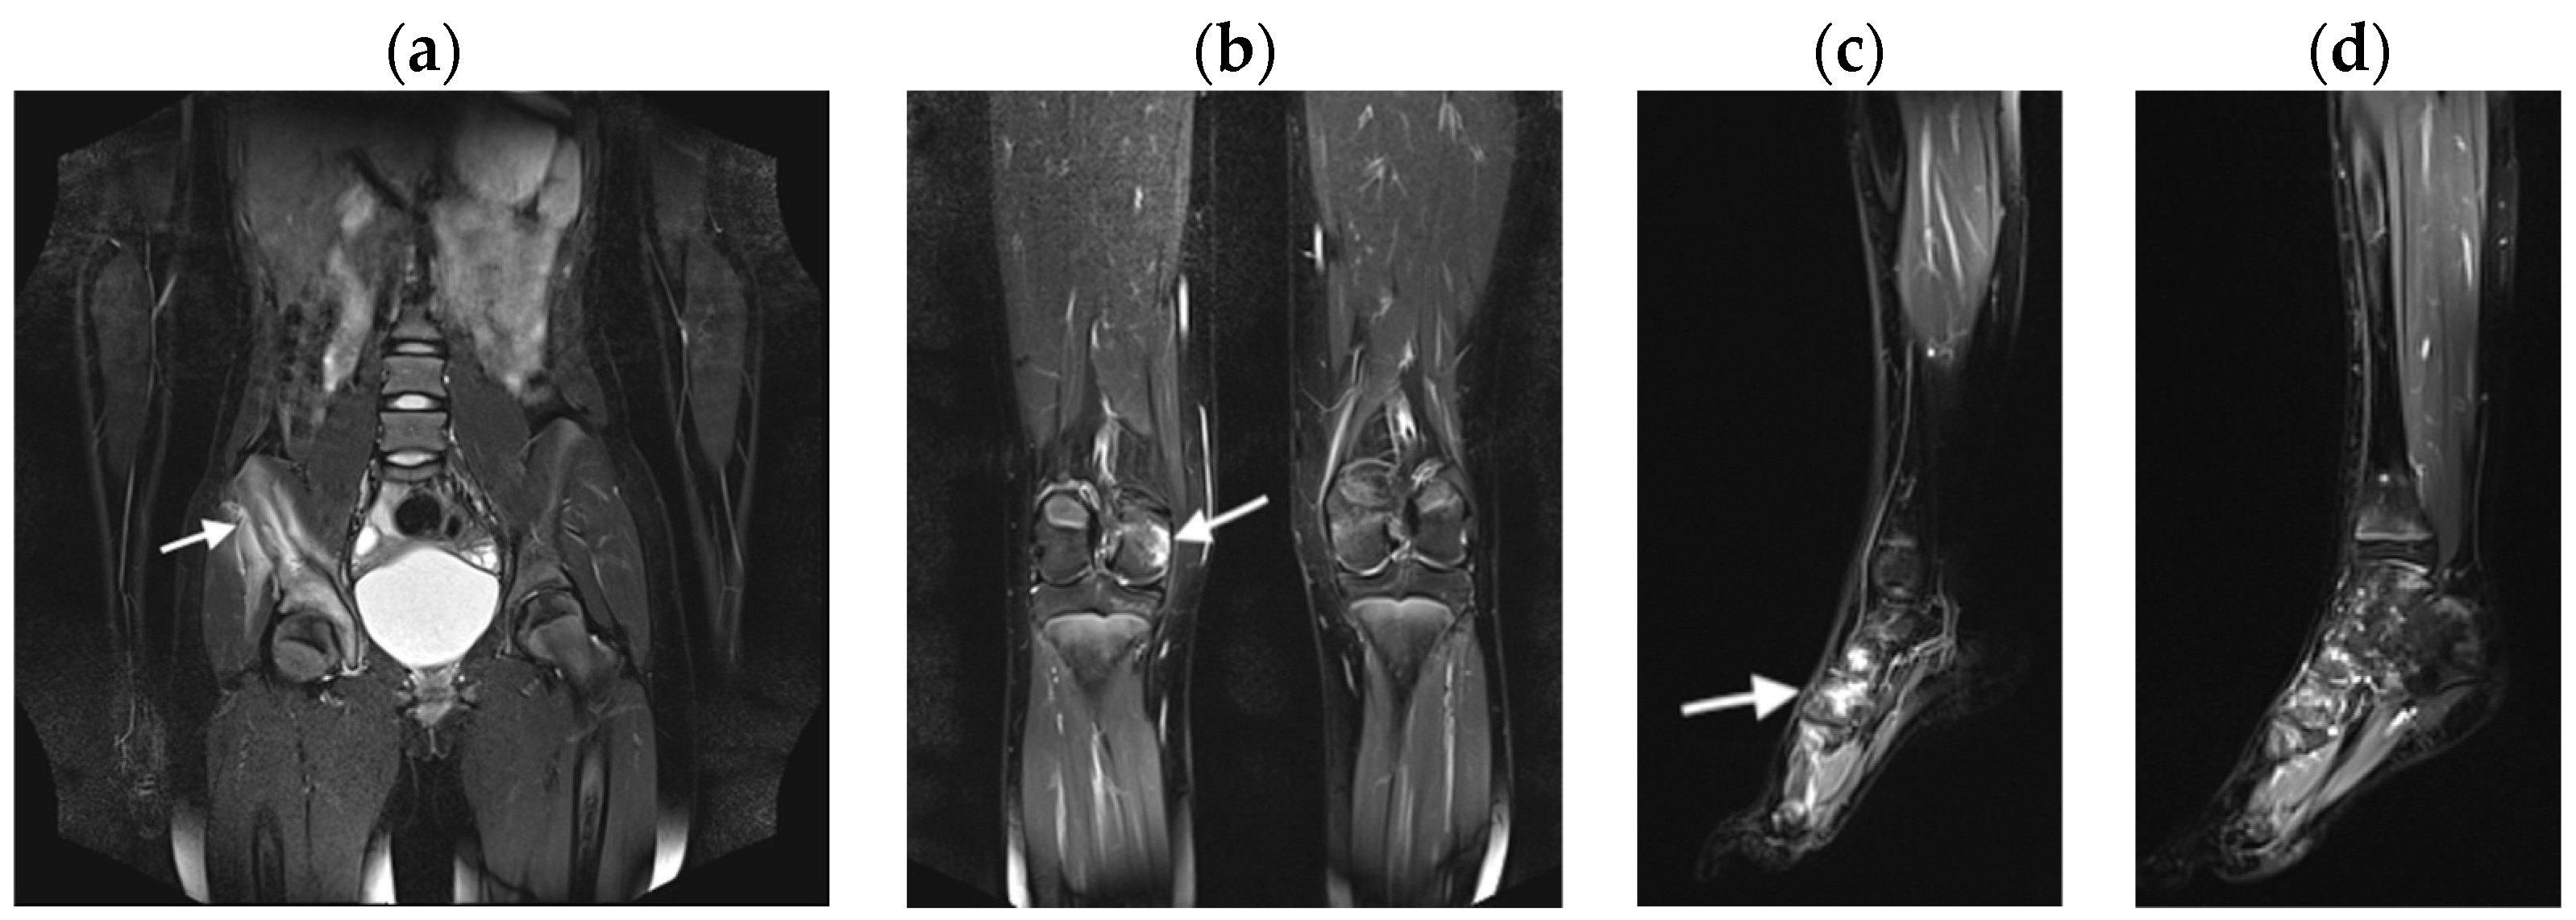

3.2.1. Bone Marrow Edema Lesions